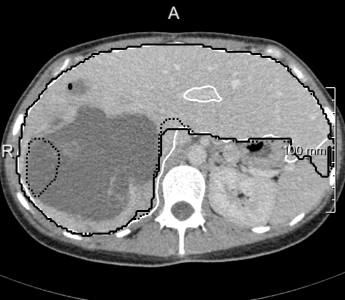

In most cases, the purely slice-wise application of the 2D U-net (dashed contours in 4) does not show any comb artifacts in orthogonal views. However, the ensemble classifier (solid contours) performs significantly better when the appearance is severely abnormal and 3D context is needed. In some cases, it locally performs worse, but has an overall better volumetric overlap (Wilcoxon signed-rank test, ). The ensemble models performed significantly better than the purely 2D transversal model on the same voxel size.

Lastly, we evaluated 3D U-nets, because slice-wise segmentation of volumetric images may lead to characteristic artifacts in general. However, both 3D U-nets performed significantly worse than the 2D ensembles. The 3D models performed better in some of the problematic areas of the 2D approaches (which were not many), but also brought new problems (5 right). We attribute this to the limits imposed by the available GPU memory on training batch sizes (2). U-nets with four resolution levels need 44 voxels of padding on each side, and when naively going from 2D to 3D (without reducing the number of filters [11, 12]), 8 GiB of memory are just enough to train with mini batches containing a single patch of 20³ voxels each, which does not suffice for stochastic gradient estimates stable enough for convergence. The ratio between the number of output voxels the loss is computed on and the number of input voxels after padding is given in the last column of 2. Consequently, the U-net performed significantly better than the 3D U-net with unpadded convolutions (Wilcoxon ).